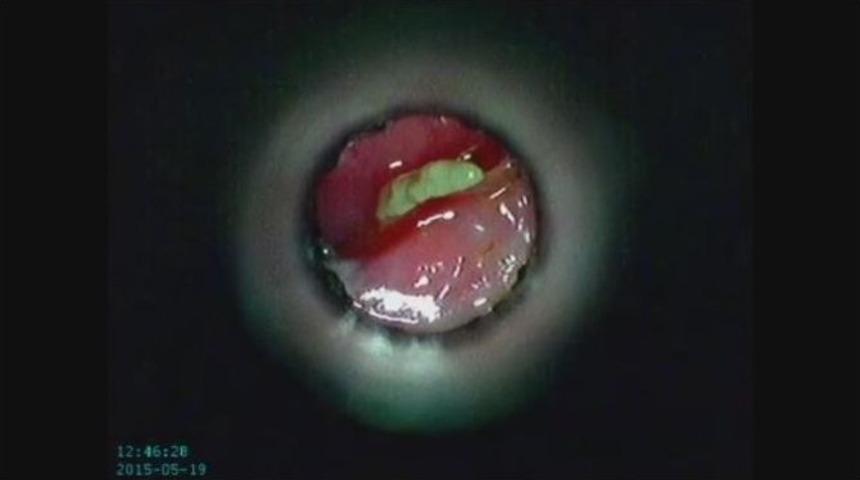

Muğla’nın Marmaris ilçesinde, burnuna ’pisi pisi otu’ kaçan bir kedi ameliyat edilerek, sağlığına kavuşturuldu.Olay, Turunç Mahallesi’nde meydana geldi. Hayvanları Koruma Derneği üyeleri, 2 yaşlarındaki dişi sokak kedisinin sürekli patisiyle burnunu kaşımasından şüphelenerek Happypets Veteriner Kliniği’ne götürdü. Yapılan kontrolde kedinin burnuna pisi pisi otu kaçtığı belirlendi. Kedinin burun köküne doğru ilerleyen pisi pisi otu başarılı bir operasyonla vücuduna ilerlemeden çıkartıldı.Ameliyatı gerçekleştiren klinik veterineri Yosun Switijnk, pisi pisi otunun hayvanların vücudunda ilerleyip hayati organlarına bile zarar verebildiğini hatırlatarak hayvan sahiplerini uyardı. Switijnk, bahar aylarında kedi ve köpeklerde pisi pisi otu kaçması vakalarının sık sık görüldüğüne değinerek, “Pisi pisi otunun başakları kuruyarak kedi ve köpeklerin burun, kulak ve pati aralıklarına giriyor. Bu ot hayvanın derin dokularına kadar ilerleyerek apse oluşturabiliyor. Özellikle evde yaşayan hayvanları yürüyüşe çıkardıktan sonra patilerini, kulak ve burunlarının kontrol edilmesi gerekiyor. Eğer kedi ve köpekleriniz başını sağa ve sola çevirip başlarını duvara sürtüyorlarsa en yakın veterinere götürmenizi tavsiye ediyoruz” şeklinde konuştu.